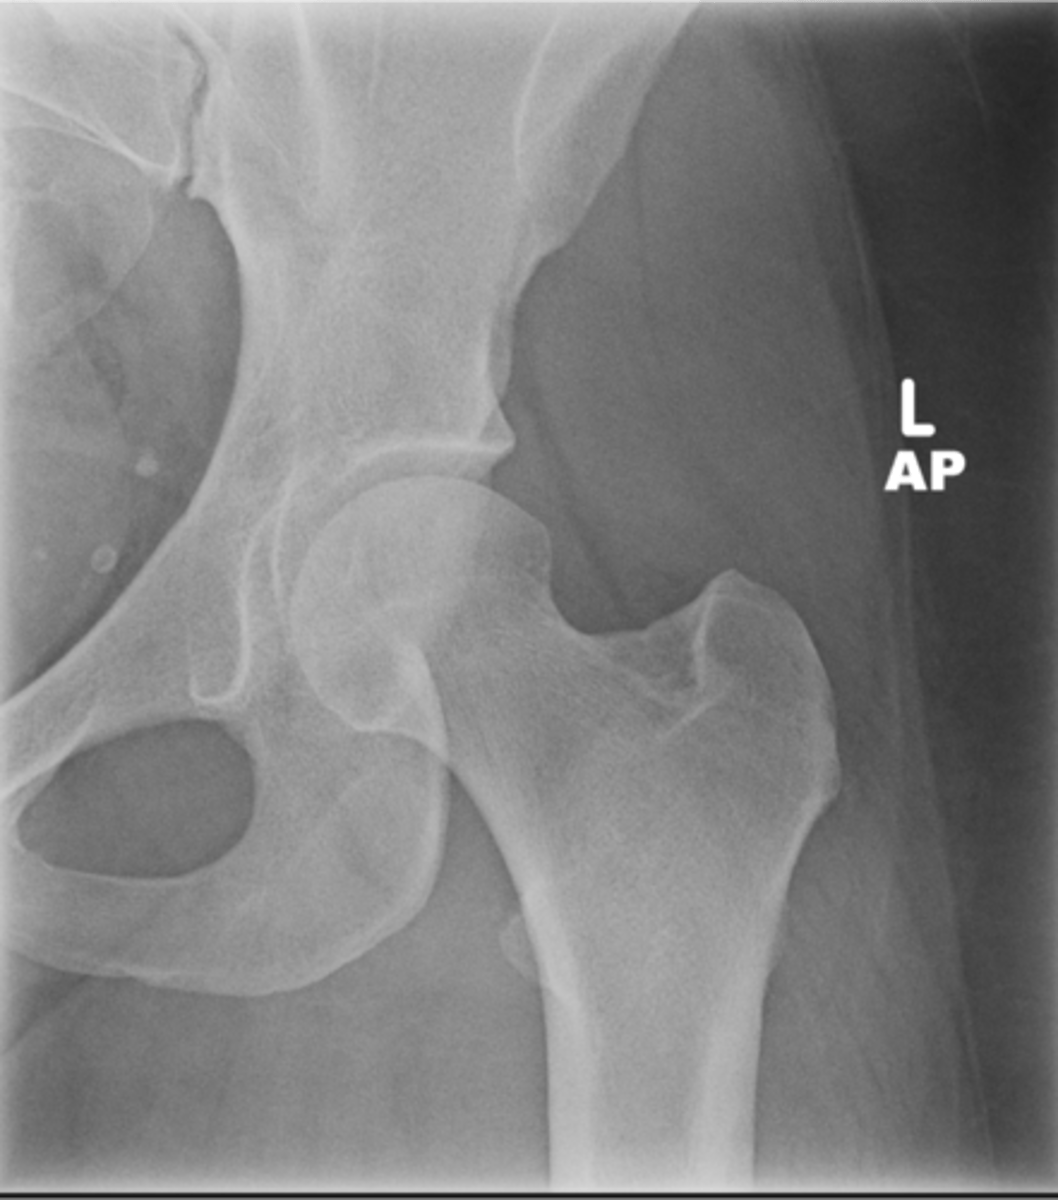

Left AP hip

View?

<p>View?</p>

29

New cards

Phleboliths

ID 1

<p>ID 1</p>

30

Obturator foramen

ID 2

<p>ID 2</p>

31

Kohler's teardrop

ID 3

<p>ID 3</p>

32

Gluteus medius

ID 4

<p>ID 4</p>

33

Ischial tuberosity

ID 5

<p>ID 5</p>

34

Acetabulum

ID 6

<p>ID 6</p>

35

Anterior inferior iliac spine

ID 8

<p>ID 8</p>

36

Lesser trochanter

37

Greater trochanter

ID 9

<p>ID 9</p>

38

Sacroiliac joint

ID 10 (joint)

<p>ID 10 (joint)</p>

39

Sacrum

ID 11 (bone)

<p>ID 11 (bone)</p>

40

ID 12

<p>ID 12</p>

41

Anterior superior iliac spine

ID 13

<p>ID 13</p>